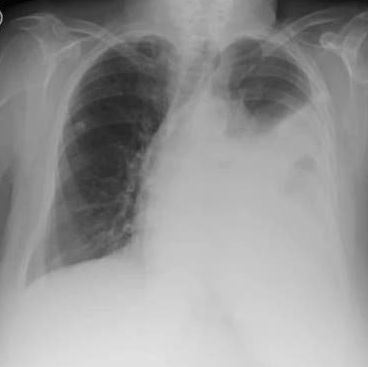

En el centro de salud de Wuhan, el muchacho se enteró de lo que le había sucedido. Había sufrido un neumotórax. El pulmón se había comprimido en un 90% y había corrido al corazón hacia el lado derecho. Allí le realizaron un procedimiento quirúrgico y lo pusieron a salvo.